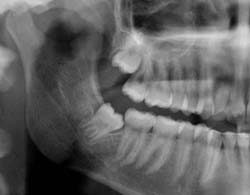

La presencia de cordales incluidos o semiincluidos puede provocar problemas como: infección local (periocoronaritis, celulitis...), daños en piezas vecinas, mal posiciones dentarias. Se aconsejaría la exodoncia cuando el riesgo de las complicaciones hace necesaria su extracción y los beneficios son mayores.